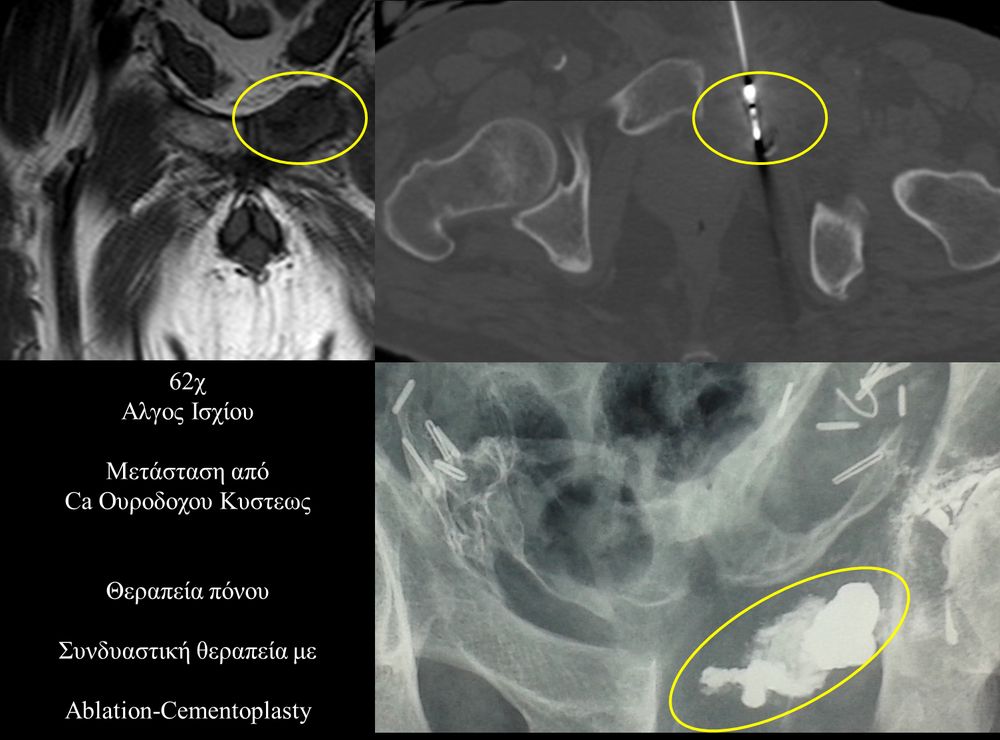

Η αντιμετώπιση του καρκινικού πόνου, εκτός από την κλασική συντηρητική φαρμακευτική θεραπεία, όταν ο πόνος επιμένει ή όταν οι παρενέργειες των φαρμακευτικών μεθόδων εξαντλούν τον ασθενή, περιλαμβάνει ελάχιστα παρεμβατικές τεχνικές με τις οποίες επιτυγχάνεται διακοπή ή καταστροφή της νευρικής οδού μεταβίβασης του πόνου. Η επεμβατική ακτινολογία διαθέτει μια πληθώρα θεραπευτικών τεχνικών που σκοπό έχουν να προσφέρουν ποιοτική βελτίωση της ζωής και των σχέσεων, τόσο των ογκολογικών ασθενών, όσο και των οικογενειών τους.